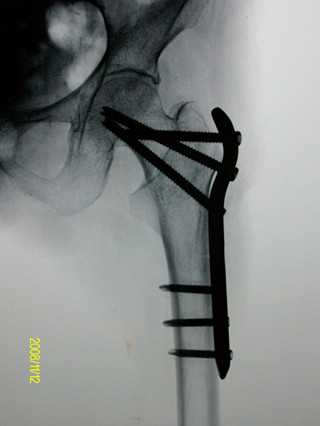

老年人髋部骨折术后